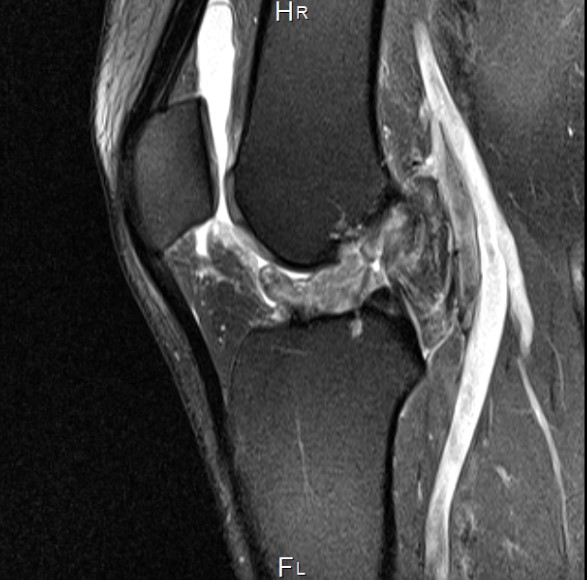

左が受傷直後、右が受傷6ケ月のMRI

治療開始が受傷後1ヶ月という急性期が過ぎつつあるということと、前十字靭帯の断裂の仕方が今までに見たことのない複雑さを呈していたことから、解剖学的自然治癒は困難であると予想していた。私の予想に反して、6ヶ月目のMRIにおいて、はっきりと靭帯の連続性が確認されたことは驚きであった。機能的には、患側に筋力低下が見られるものの、日常生活においては問題ないレベルまで回復している。患側の筋力が戻るまでリハビリは継続していく予定である。

He ruptured his right ACL completely in December,2018. He started the Naturalization Therapy from the one month after the injury. We had the internet sessions through the Skype once in every 2 weeks for the first 3 months and once in 1 month from the 4 months. At first, there were the difficulties for the anatomical healing, because it was the severe and complete ACL tear which had torn in the unusual way. Moreover, it was late that he started my therapy because the acute period was almost passing. Contrary to my expectations, the MRI shows that his completely torn ACL has healed clearly and anatomically. The Naturalization Therapy enables the ACL tear to heal naturally without any complication. As long as the blood supply and the anatomic reduction are secured, the natural healing process will work even on the ACL.